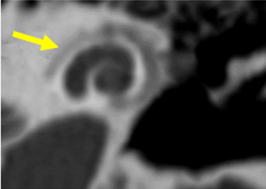

Figura 5. Ventana oval obliterativa de oído derecho en un corte coronal de oído medio |

El estado de la ventana redonda es importante, ya que su afectación se asocia a un mayor riesgo de hipoacusia neurosensorial posquirúrgica. La obliteración de la ventana redonda, aunque no se frecuente, puede diagnósticarse preoperatoramiente y podría contraindicar el tratamiento quirúrgico (Fig.6).

Figura 6. Oídos derechos con obliteración de ventana redonda (flecha amarilla) |

Tamaño del nicho de la ventana oval: Valores de 1,4 mm se toma como límite inferior de la normalidad. Valores menores se asociaban con un riesgo mayor de tener dificultades técnicas durante la cirugía del estribo. Debe descartarse una otosclerosis obliterativa (Fig. 4-5). |